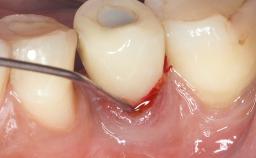

Resective Surgical Treatment of Peri-Implantitis Including Implantoplasty

In this case, Myroslav Solonko, Ignacio Sanz Sánchez and Mariano Sanz present a treatment that aims to eliminate exposed implant threads by modifying the implant surface, converting a moderately-rough surface into a smooth surface.

A 63-year-old male patient was referred to the post-graduate periodontal clinic of the Complutense University of Madrid for the treatment of peri-implantitis. According to the patient’s record, all his maxillary teeth had been extracted ten years previously due to severe periodontitis, and a full-mouth implant-supported restoration on eight implants was placed. No supportive periodontal therapy was provided apart from occasional check-ups by the restorative dentist.